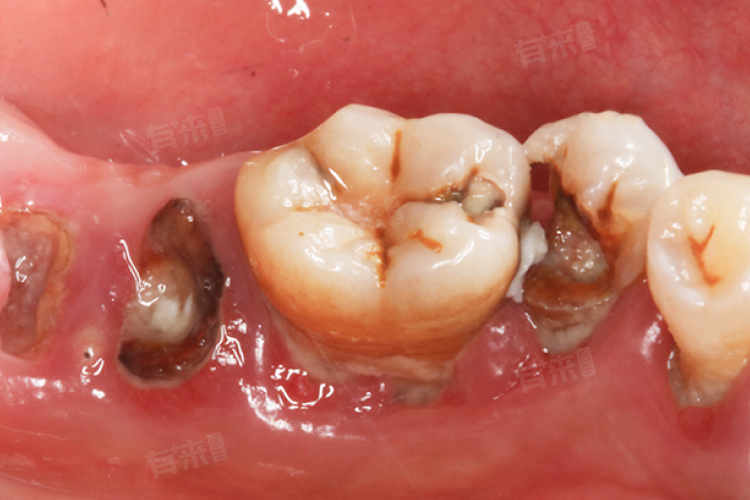

2、损伤程度:给牙齿带来明显损伤,牙齿可能有较大的破洞以及多处菌斑。

3、临床症状:牙齿上会有一个黄褐色、棕褐色等不同颜色的洞。并且在牙齿未受到刺激时就有疼痛感,并且在受到冷、热、外力等刺激后有疼痛加重的情况。由于深龋的龋洞较大、较深,容易嵌塞食物残渣,这些食物残渣被细菌分解后会产生异味。